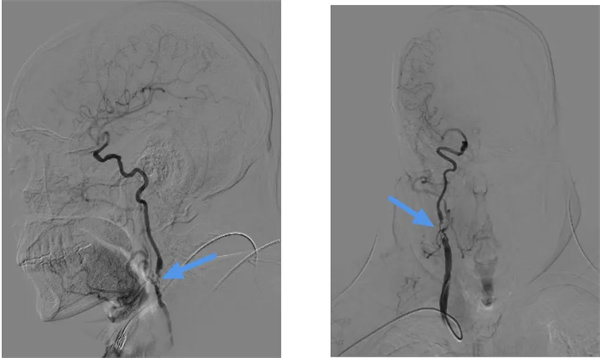

64歲的劉先生,因為長期間斷頭暈不適,發作時天旋地轉,在外院就診查頸部血管B超提示:雙側頸總動脈粥樣硬化合并斑塊形成,右側頸內動脈狹窄。在我院行DSA檢查:右側頸總動脈分叉部及頸內動脈起始處后壁鈣化斑塊伴重度狹窄,狹窄率約95%。

患者右側頸動脈重度狹窄,隨時可能閉塞,如果不及時處理,可能引起大面積腦梗死,出現嚴重后遺癥,輕者出現偏癱長期臥床,嚴重的引起昏迷。醫務部組織疑難病例MDT討論,麻醉科、神經內科、介入科、心血管內一科、影像科、功能科等科室參加討論,制定最佳治療方案。經過充分的術前準備,由神經外科血管組團隊為患者實施了頸動脈內膜剝脫術(CEA),術前彩超定位頸動脈分叉位置,利用顯微技術,通過頸前5cm小切口暴露右側頸總動脈、頸內動脈、頸外動脈等結構,仔細剝離并切除增厚的內膜斑塊。術中由功能科全程腦血流監測,保障手術安全進行。整個手術過程用時短,出血量?。▋H5毫升左右)。術后嚴密觀察患者血壓以及頸部切口情況,規范血壓管理,預防血流高灌注和術后出血等相關并發癥。目前術后1周,患者恢復良好,原有頭暈癥狀已消失,取得了預期效果。